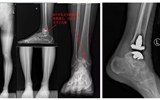

立博欧赔指数第二医院骨科完成甘肃省首例INBONEII全踝关节置换手术